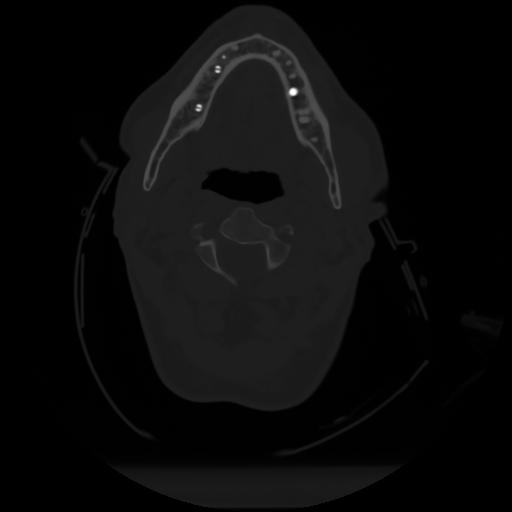

10 P.BLANDAS,,Axial,2.0,P.BLANDAS,,